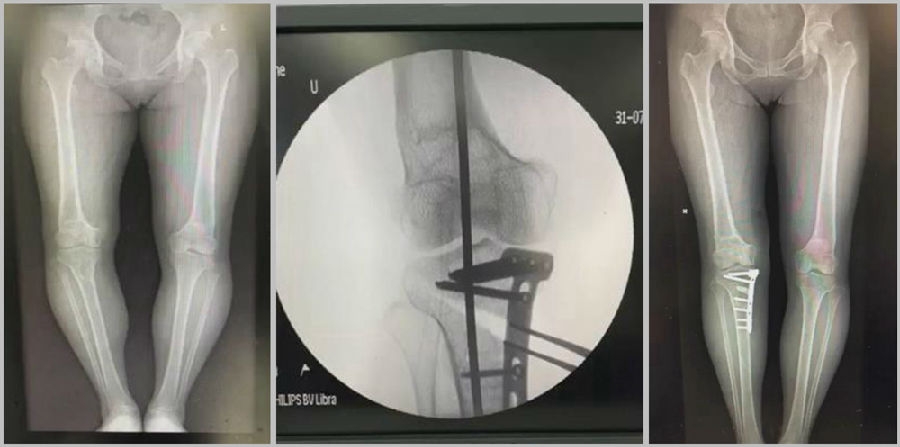

二、矫正不良

截骨实际上是通过力线的重新分布来调整好关节的压力,但是经常会出现矫正过度或者矫正不良的问题。

1、综合判断力线的方法

现在对于力线的判断大致通过以下几方面:①大体形态;②透视确定力线,连接股骨头中心、踝关节中心,看力线杆和膝关节中心的位置关系;③MPTA(胫骨平台关节线和胫骨侧机械轴夹角);④PSI。

1、原因及预防

(1)肢体外旋

一般来说在麻醉状态下肢体会处于外旋位,此时去测定力线的话往往需要将肢体放在旋转中立位,但是在内旋肢体的过程中会出现内翻应力,那么这种情况下判断力线会带来误差,所以通常建议大家要把手术床做一点旋转,让患肢处于自然的旋转中立位,这样再去判断力线就比较准确。

(3)力线验证未模仿负重应力

现在所谓的目标力线应该是模仿负重时的力线。做截骨时,通常会将力线轻度外移,如果没有考虑关节内畸形、韧带松弛或是软骨磨损,那么在负重时,在内侧副韧带撑开过程中,会出现力线偏移。所以要注意,手术中间在调整目标力线时,要以应力状态下为标准。